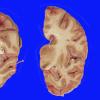

Subcortical Arteriosclerotic Encephalopathy (6)